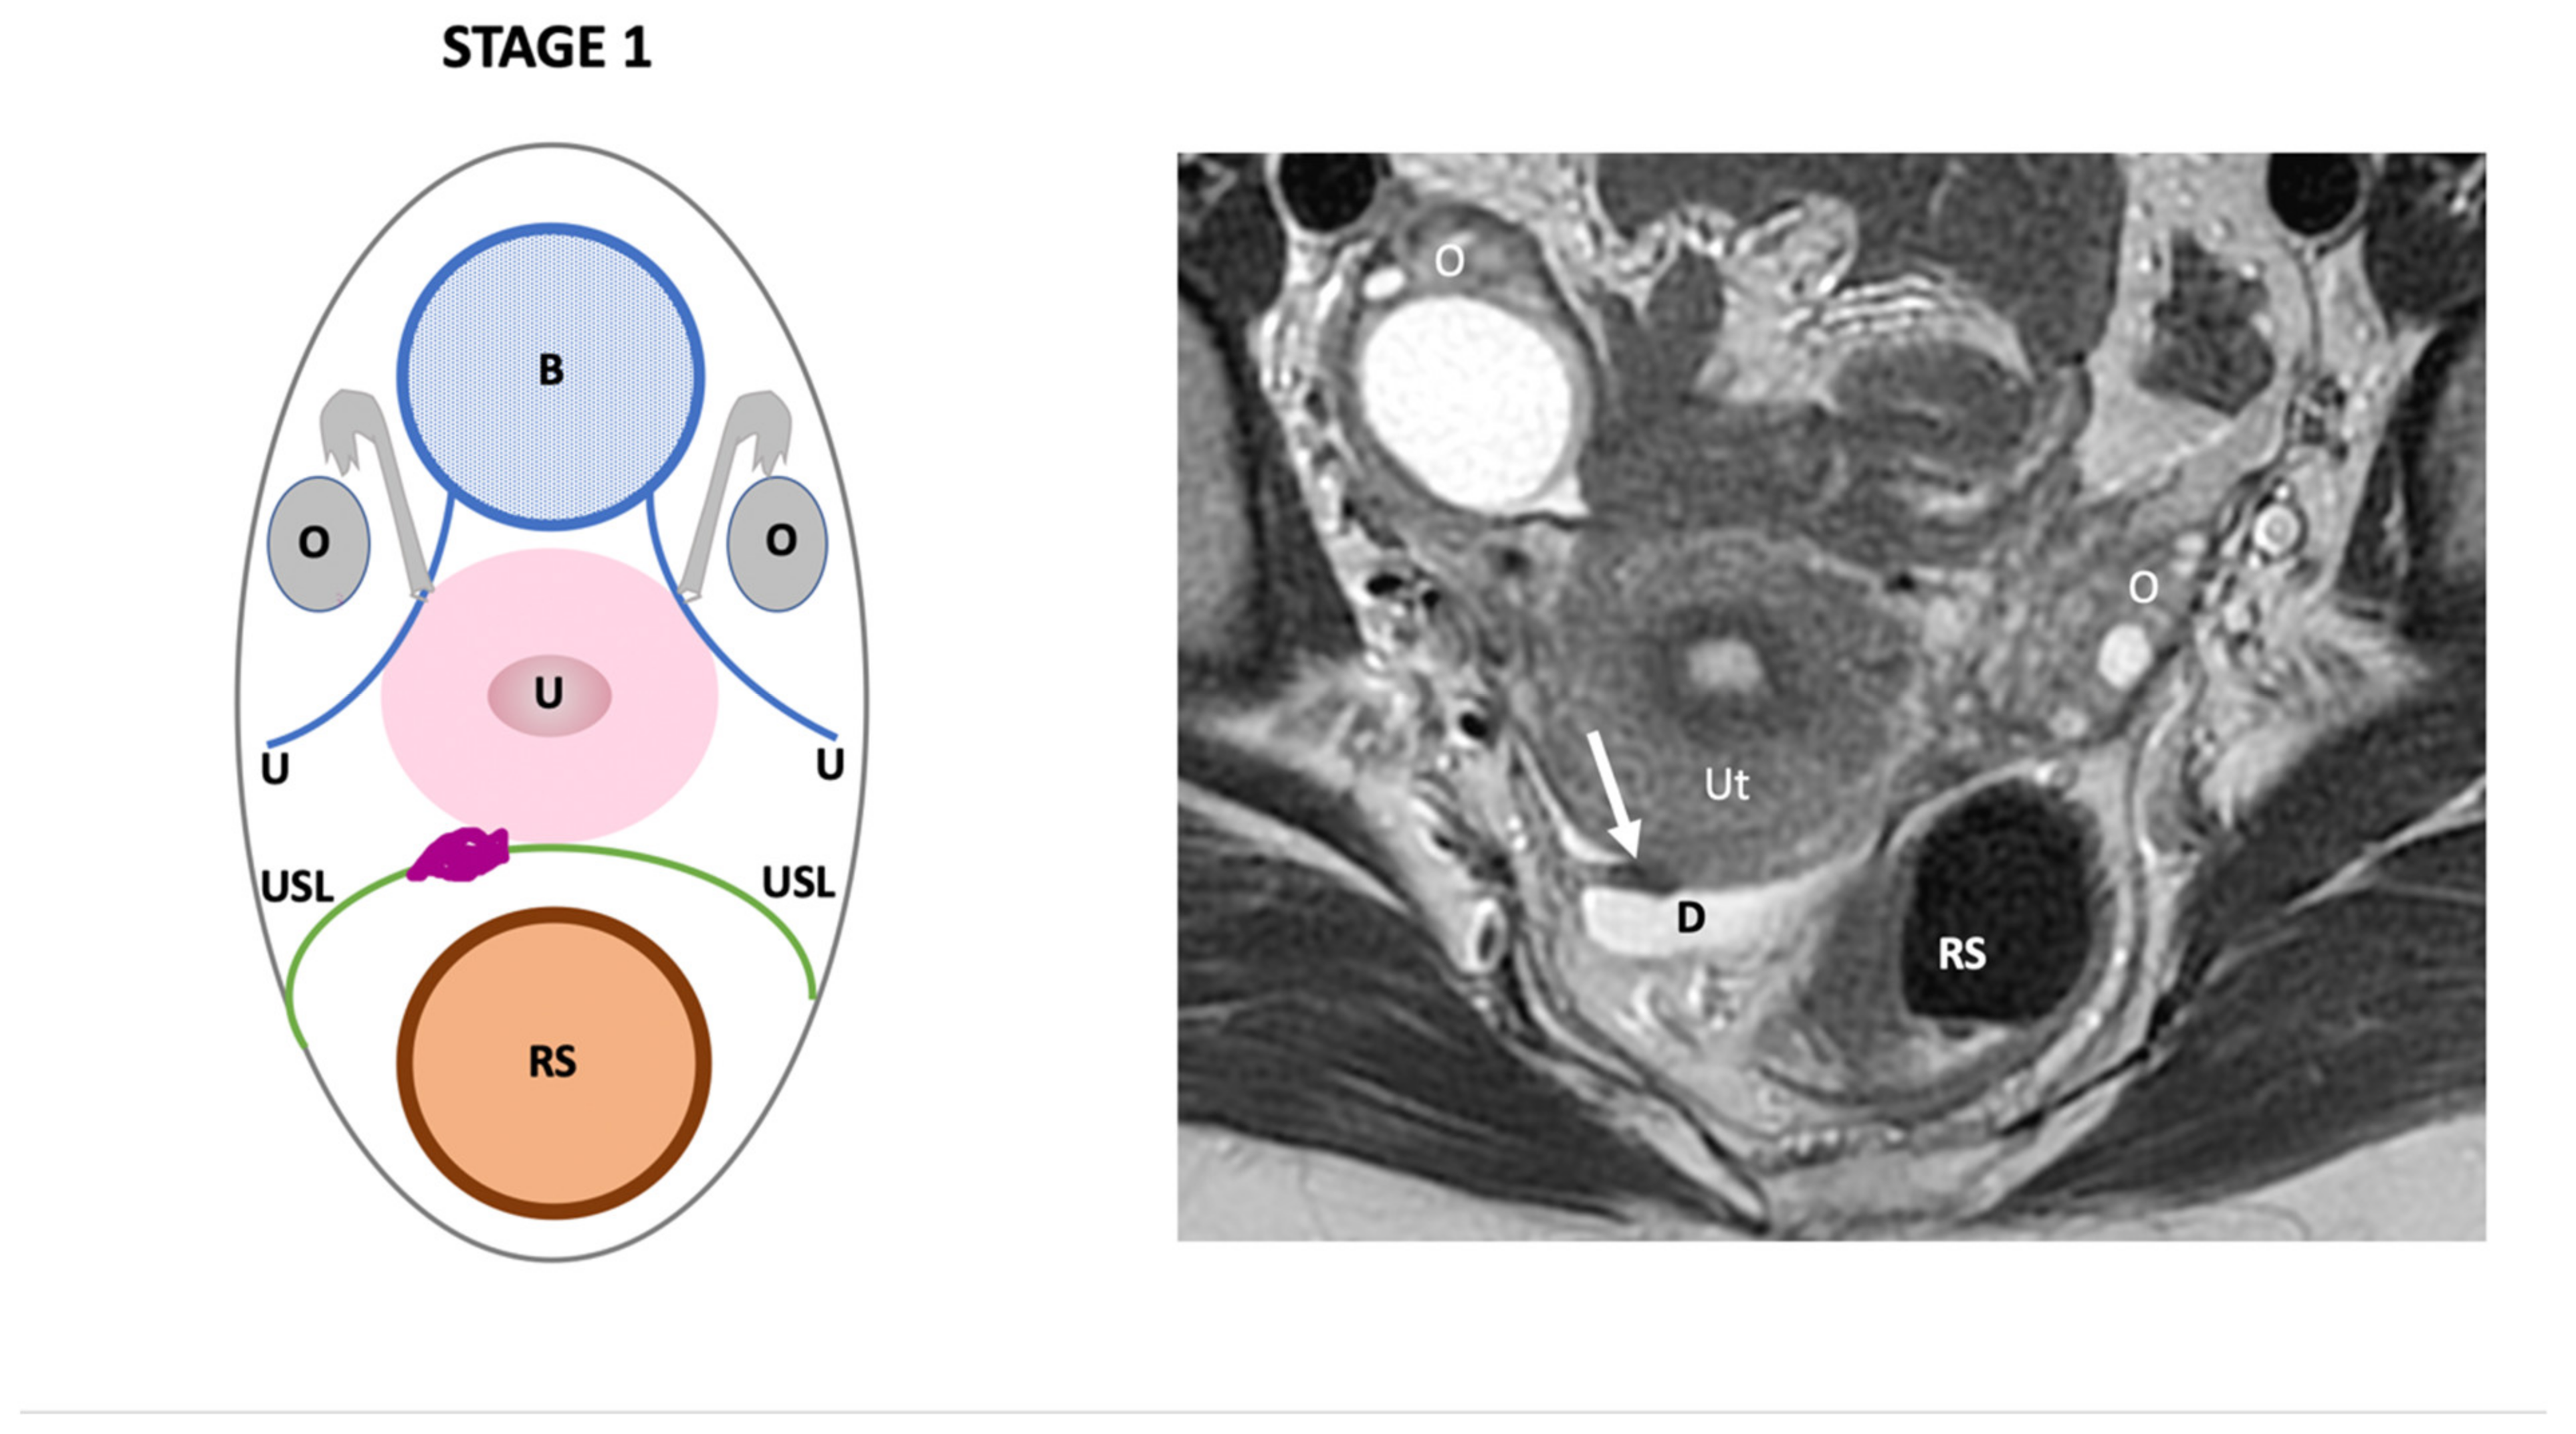

3. The Endo-Stage Mri Classification

| Endo-Stage MRI | Location | Extent | Risk Stratification |

|---|---|---|---|

| Endo-Stage MRI 0 | Superficial endometriosis |

| Low |

| Endometriosis is strictly confined to the ovaries |

| ||

| Endo-Stage MRI I | Endometriosis is strictly confined to the retrocervical area |

| |

| Endo-Stage MRI II | Endometriosis invades beyond the retrocervical area, but not to the pelvic side-wall |

| Endo-Stage MRI III | Endometriosis extends to the pelvic side-wall and/or causes hydronephrosis or non-functioning kidney |

| Intermediate |

| Endo-Stage MRI IV | Endometriosis has involved the bladder or rectosigmoid colon |

| Endo-Stage MRI V | Multiple deep endometrioticlocations |

| High |